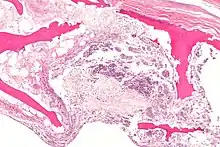

In addition, the Association Research Circulation Osseous (ARCO) suggested a new classification system based on the combination of radiographic, MRI, bone scan and histologic findings. However, apparently these two classifications systems, Ficat and ARCO are still not enough reliable to assess the status of ONFH alone.[2]